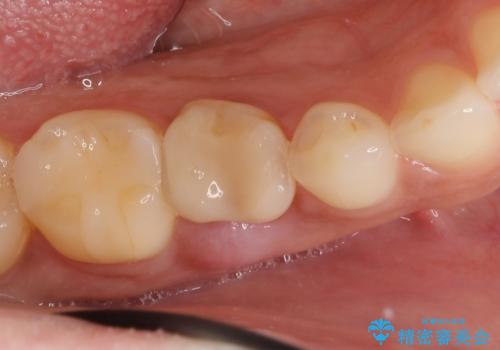

- 40万円(ストローマンインプラント・カスタムジルコニアアバットメント・ジルコニアクラウン)費用は治療当時の料金となります

大人になっても残っている乳歯は根管治療や他の治療で残せる場合もありますが、今回のように状態が悪い場合早期に抜歯をすることで歯槽骨が温存でき十分に安定した骨量でインプラントによる機能回復を達成することができました。